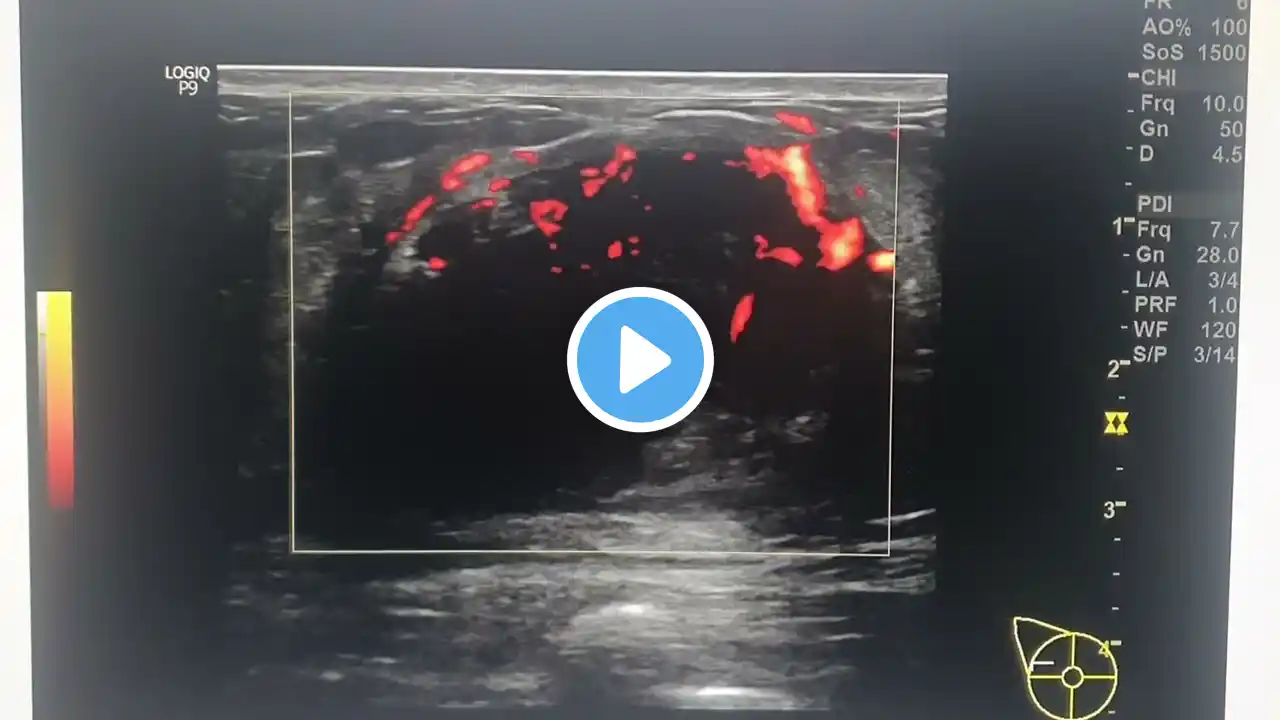

IBU Ultrasound of Invasive Lobular Carcinoma StavrosTRIMMED